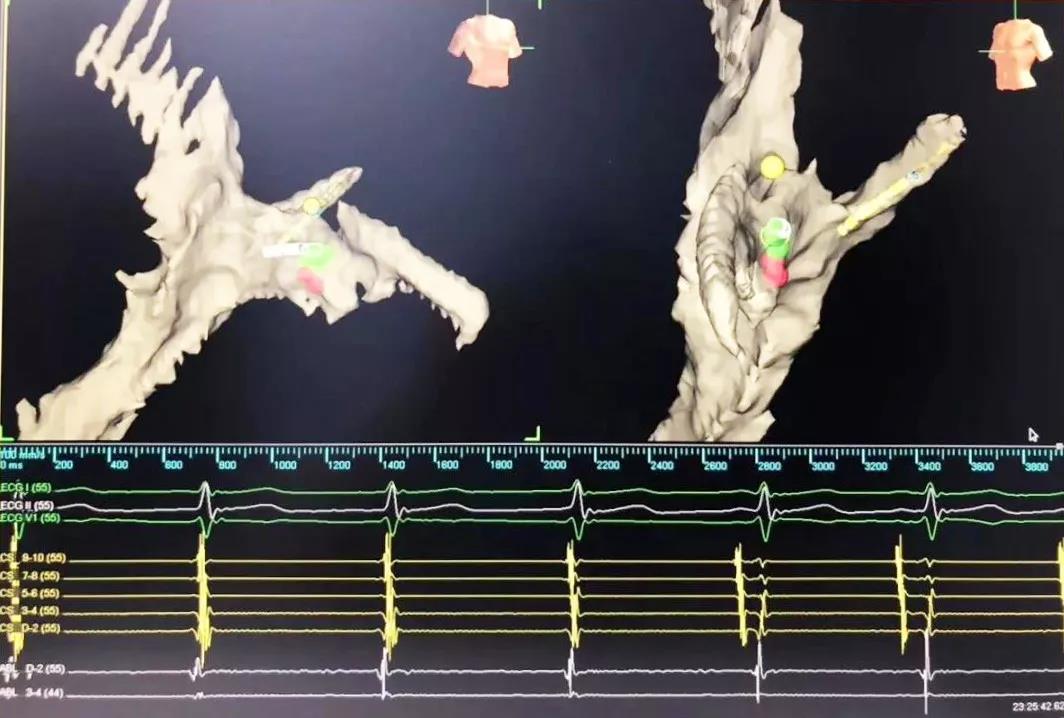

又一道難題擺在眼前,常規(guī)手術(shù)需要在X射線下進行,X射線會導(dǎo)致胎兒發(fā)育畸形。在心臟病醫(yī)院院長王海昌的帶領(lǐng)下,專家團隊仔細研究后,決定為張女士施行三維標測系統(tǒng)指引下零射線心臟電生理檢查及射頻消融術(shù)。

在完成常規(guī)檢查,排除新型冠狀病毒肺炎的可能后,217日,由廉誠主刀,在三維標測系統(tǒng)指引下行零射線心臟電生理檢查及射頻消融術(shù)。術(shù)中明確患者心動過速為房室結(jié)折返性心動過速,遂行房室結(jié)慢徑改良,消融完畢后反復(fù)刺激驗證,心動過速均不能誘發(fā),手術(shù)成功,歷時約1小時,全程零射線完成。這也是西安國際醫(yī)學(xué)中心醫(yī)院心臟病醫(yī)院的首例零射線治療特殊人群心律失常病例。